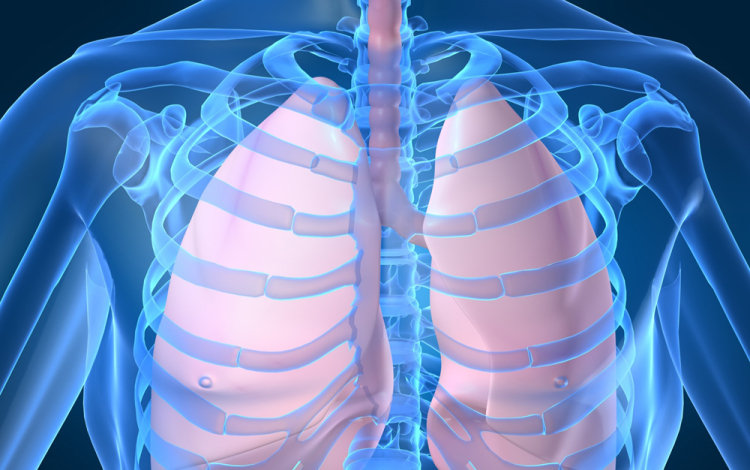

Húszan várnak tüdőátültetésre Magyarországon

Húszan várnak tüdő-transzplantációra az országban, tavaly 12 magyar betegen hajtottak végre ilyen szervátültetést külföldön

- mondta Kásler Miklós, az Országos Onkológiai Intézet főigazgatója vasárnap az M1 aktuális csatorna esti műsorában. A főigazgató ezt azzal kapcsolatban közölte, hogy még idén elvégezhetik az első tüdőátültetést Magyarországon.

Magyarországról tavaly 37 tüdőt szállítottak Bécsbe átültetési céllal; ha nálunk is elérhetővé válik a műtét, akkor várhatóan a környező országokból is Budapestre érkezik majd a betegek egy része Bécs helyett - mondta a főigazgató.